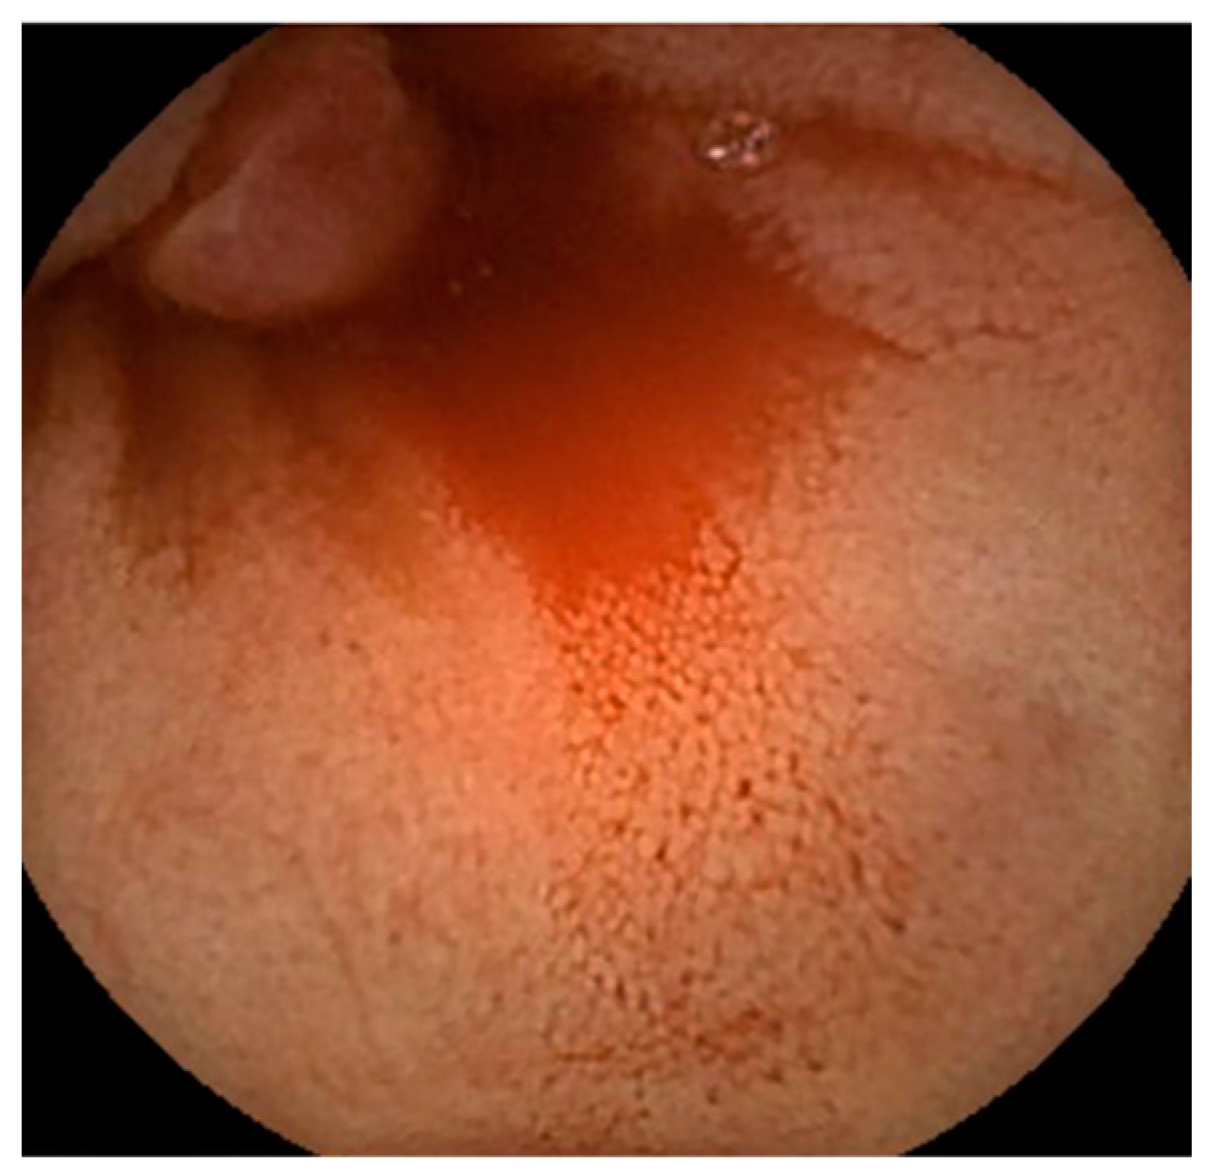

Abdominal contrast-enhanced computed tomography, gastroscopy, and colonoscopy were performed; however, no evidence of bleeding was found. An SBCE (PillCam® SB3, Covidien Japan Ltd., Tokyo, Japan) revealed a reddish polypoid lesion with blood oozing into the jejunum (Figure 1). We performed an antegrade DBE (EN-580T®, Fujifilm, Tokyo, Japan) to detect the cause of the bleeding and achieved endoscopic hemostasis. The DBE revealed a 5 mm sized protrusion into the jejunum about 200 cm distal from the Treitz ligament (Figure 2). The surface of the lesion was covered with mucus and slightly reddish compared to the surrounding mucosa.

Figure 1. A reddish polypoid lesion and blood oozing into the jejunum as found by small bowel capsule endoscopy.